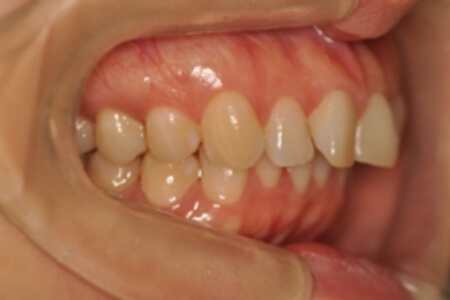

でっ歯(非抜歯)【2104】

治療内容の詳細 初診時30歳の女性で、全体的ながたつきを主訴として来院されました。

検査の結果、過蓋咬合を伴う、アングルⅡ級1類不正咬合と診断しました。

治療としては、非抜歯の上、セルフライゲーションブラケット装置(デーモンシステム)とマウスピース矯正装置(インビザライン)で歯の配列を行いました。

同時に顎間ゴムにて咬合関係の改善を行いました。